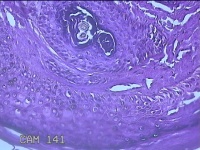

左眼外侧缘上肿物

性别

女

年龄

60岁

临床诊断

痣;疣

左眼上睑缘白色丘疹1年余。

大体所见

图1